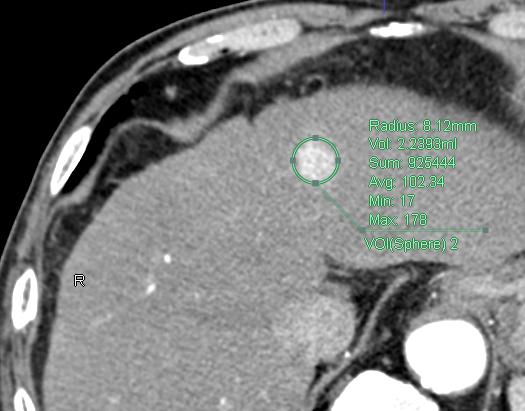

VOI

関心領域(Volume of Interes)

画像の中で認識処理を適用したい範囲、特定の領域のことです。

ROIとほぼ同義であり、3次元的な(z軸方向も含めた)範囲や領域のことを指します。

REVORASやZiostation2では、球形のVOIが使用可能です。